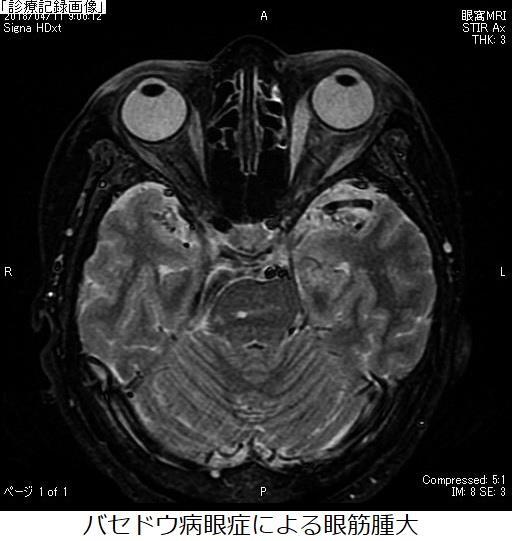

白内障、緑内障、糖尿病網膜症、網膜静脈閉塞症、黄斑円孔、加齢黄斑変性症、ドライアイ、眼瞼下垂、眼瞼痙攣、顔面痙攣、複視、甲状腺眼症